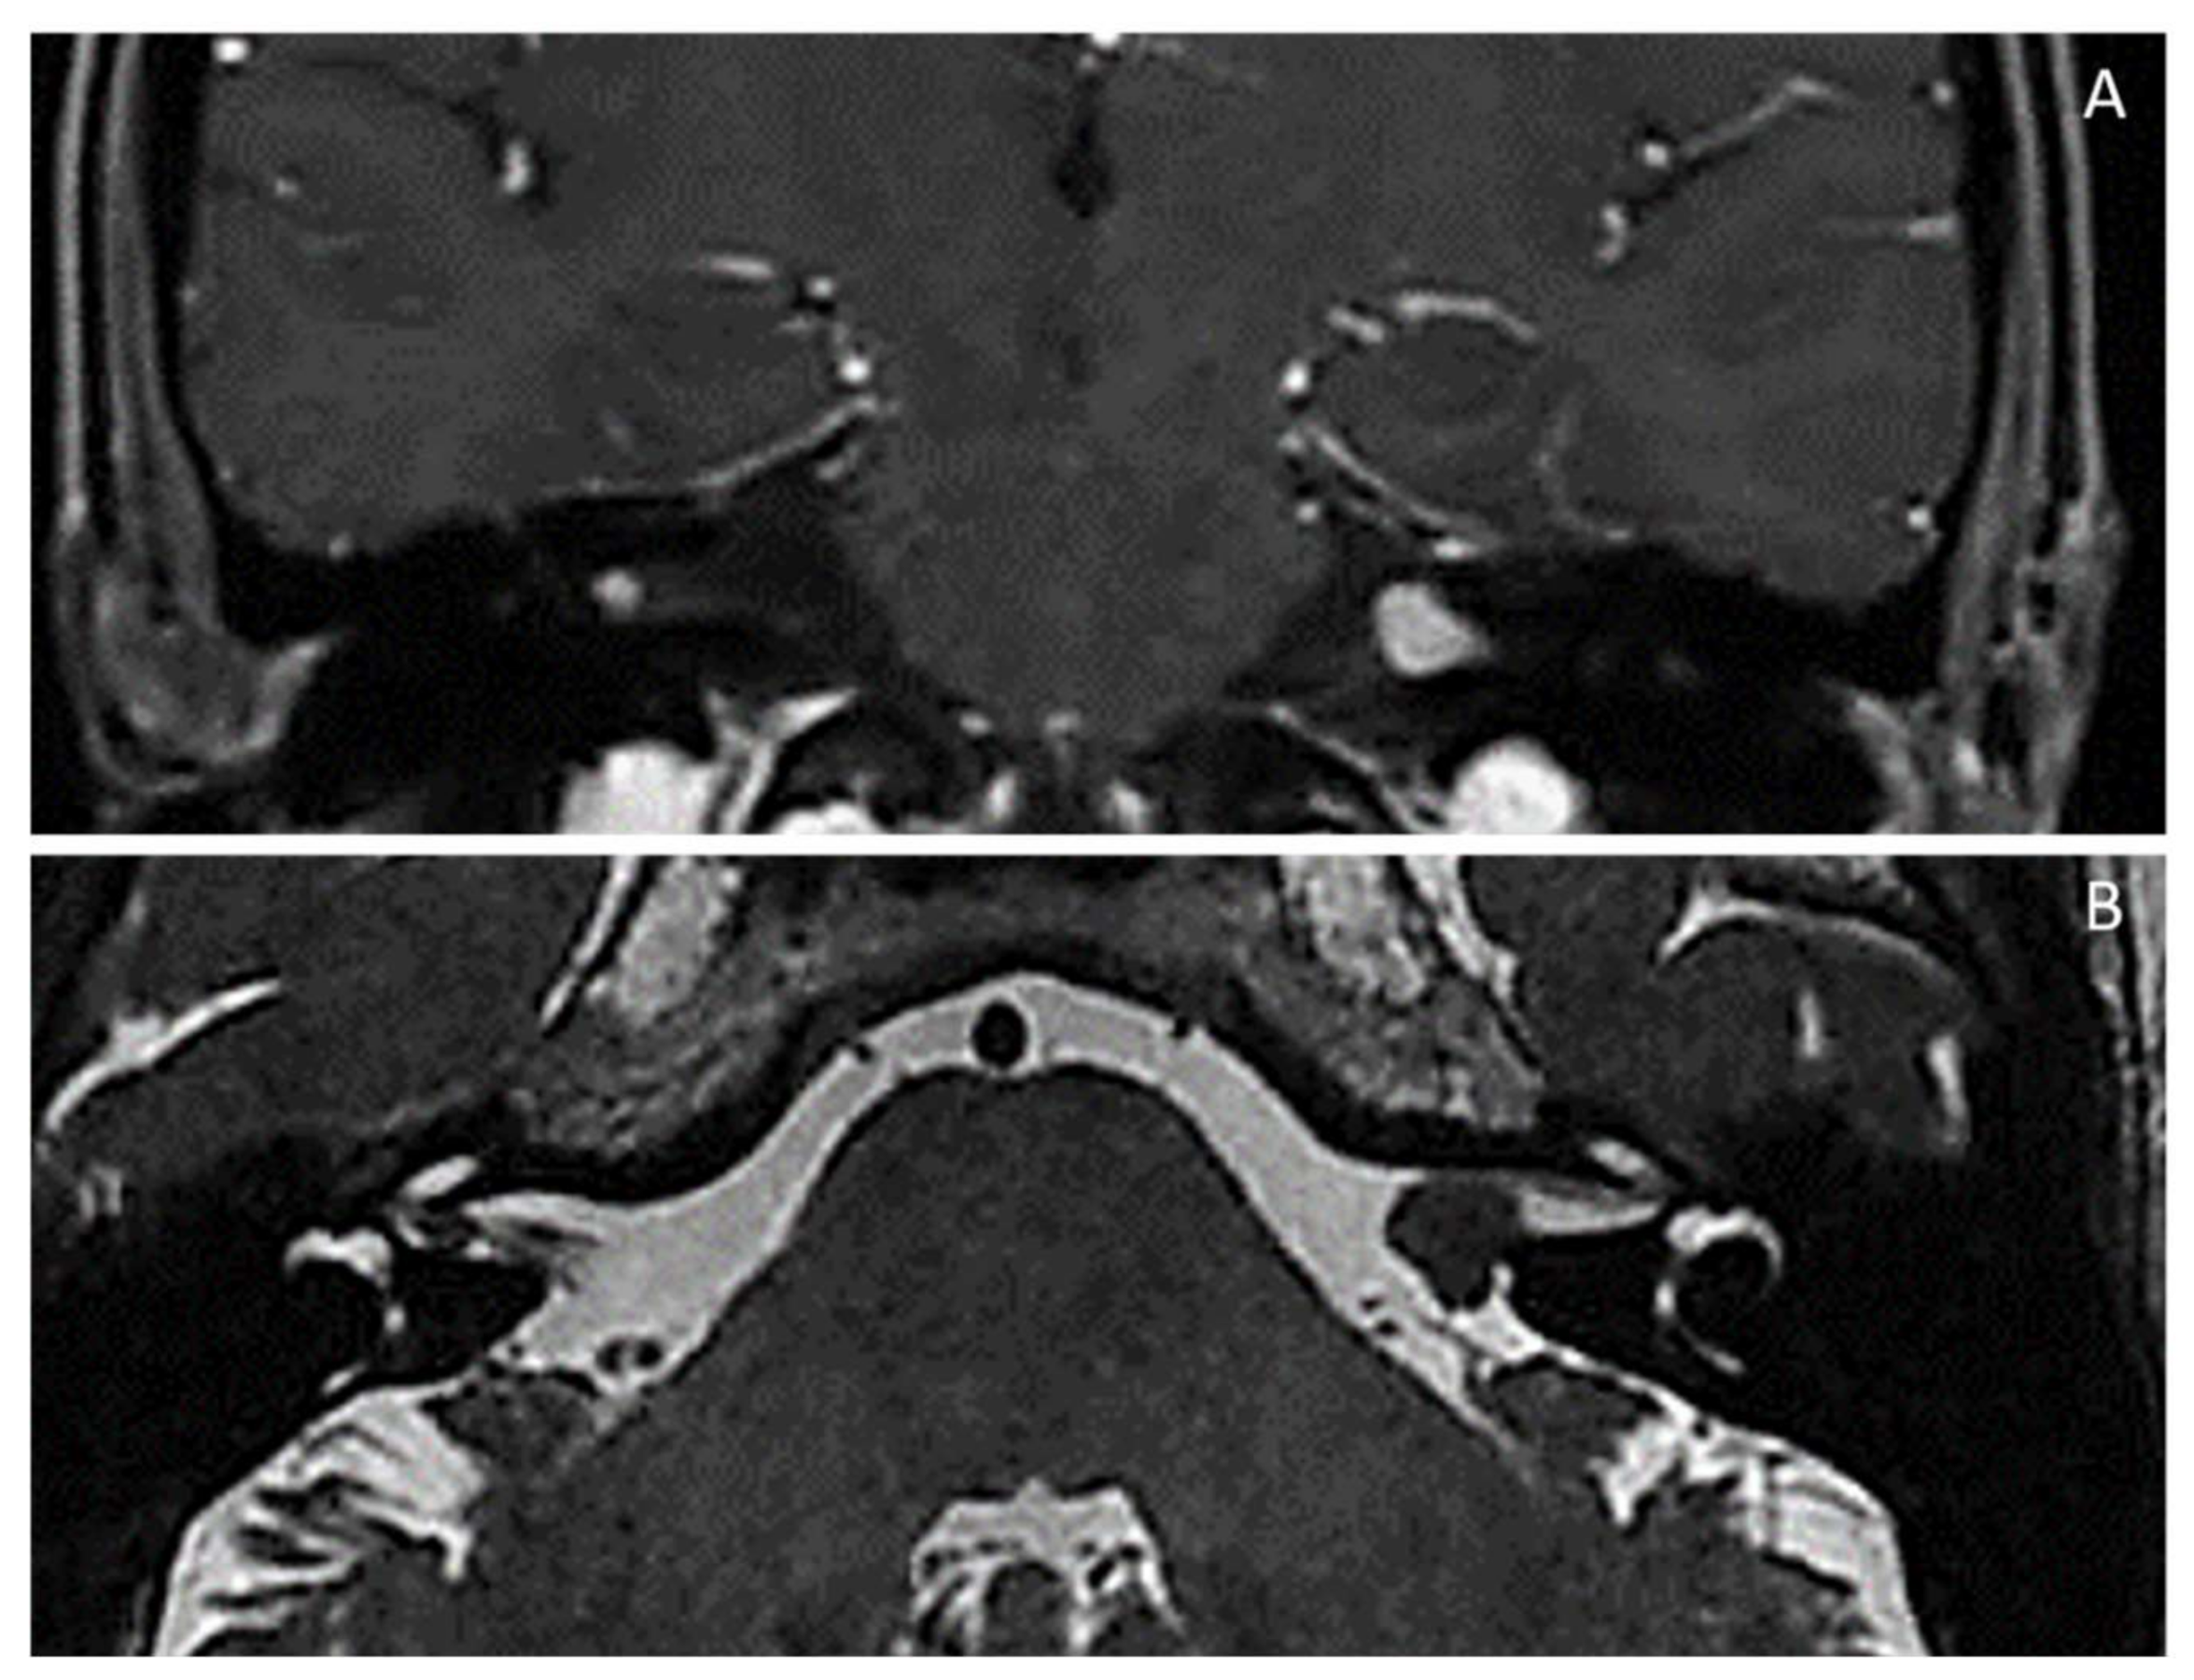

| NF2-related schwannomatosis [NF2/MERLIN-schwannoma predisposing syndrome (NF2/MERLIN-SPS)] (Previously, neurofibromatosis type 2 or NF2) [MIM # 101000; ORPHA:637] Chromosome 22q12.2 (NF2/MERLIN moesin-ezrin-radixin-like gene): identical NF2 gene pathogenic variant in at least two anatomically distinctNF2related tumours (e.g., schwannoma, meningioma and/or ependymoma); NF2 gene variants in unaffected tissues (e.g., blood) and major/minor criteria (see below); Main features: (1) Gardner type (adulthood): Bilateral (or, sometimes, unilateral) VIII cranial nerve (vestibular) schwannoma(s) *; schwannomas of cranial nerves *; multiple meningiomas, ependymomas, schwannomas *; early-onset (posterior subcapsular or cortical) cataracts *; skin schwannomas (NF2 plaques) *; nodular schwannomas *; (2) Wishart (severe) type (childhood): prior to appearance of VIII nerve schwannomas * and/or nervous system tumours (meningiomas, ependymomas) *, non-VIII-cranial nerve schwannomas (e.g., mixed nerves, V, VII) *; early-onset (posterior subcapsular or cortical) cataract *; epiretinal membranes/hamartomas *; skin schwannomas (NF2 plaques) * diffused over body; brain cortical dysplasia; bone dysplasia; (3) Congenital type (neonatal/< 1 year): small bilateral VIII nerve schwannomas * stable for decade(s); optic nerve sheath meningioma(s) *; epiretinal membranes/hamartomas *; early-onset (posterior subcapsular or cortical) cataract *; skin schwannomas (NF2 plaques) * in atypical places (face, arms, legs) later disappearing; ependymomas *; spinal cord schwannomas and meningiomas *; brain cortical dysplasia; |